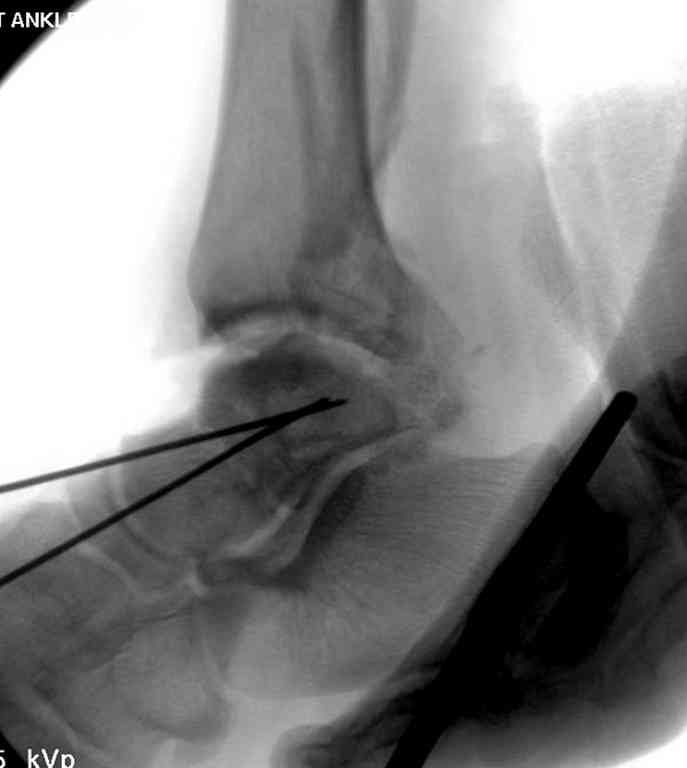

10 дней назад поступил с открытым повреждением медиальной лодыжки и переломо вывихом таранной кости. Ургентно сделана репозиция с наложением наружного фиксатора + Irrigation&Debridment.

Вчера провели фиксацию.

Из-за многооскольчатости дистальной части малоберцовой, где невозможно было провести фиксацию шурупами, перелом зафиксирован подпирающей пластиной, которая должна служить дополнением отсутствующей дистальной части малоберцовой (lateral cortex substitute).

Для стабильности два шурупа на синдесмоз.

Медиальную рану с приближенными краями продолжаем вакуумировать (KCI). Наружный фиксатор оставлен на пару недель, надеюсь, небольшая рана будет гранулировать и закроется без кожной пластики. Фиксация медиальной ложыжки не планируется.